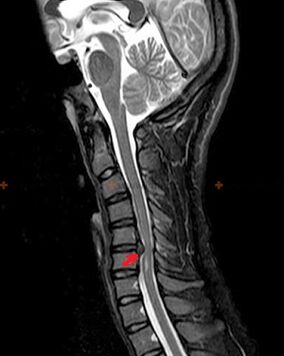

Diagnostica e segni radiografici

L'osteocondrosi è una diagnosi radiografica, poiché un quadro clinico dettagliato è disponibile solo al momento dell'esacerbazione, mentre i cambiamenti nella colonna vertebrale possono verificarsi con il completo benessere soggettivo di una persona. Senza un esame radiografico si può parlare solo di sospetta osteocondrosi, perché sintomi simili possono essere causati da altre malattie (miosite, neoplasie vertebrali e altre).

Per diagnosticare l'osteocondrosi vengono utilizzati i seguenti metodi di ricerca: radiografia (preferibilmente con test funzionali), MSCT e MRI. Quest'ultimo studio è preferibile perché consente di visualizzare molto chiaramente lo stato delle strutture intervertebrali.

I segni radiografici dell'osteocondrosi includono i seguenti cambiamenti nella colonna vertebrale:

- Altezza ridotta dei dischi intervertebrali.

- Presenza di escrescenze ossee marginali.

- Violazione della posizione delle vertebre l'una rispetto all'altra.

- Deformazioni dei corpi e degli archi vertebrali, ecc.

La presenza dei cambiamenti sopra descritti, così come i cambiamenti nella struttura del disco intervertebrale, rilevati mediante MSCT e MRI, servono come segni affidabili che confermano la presenza di osteocondrosi.